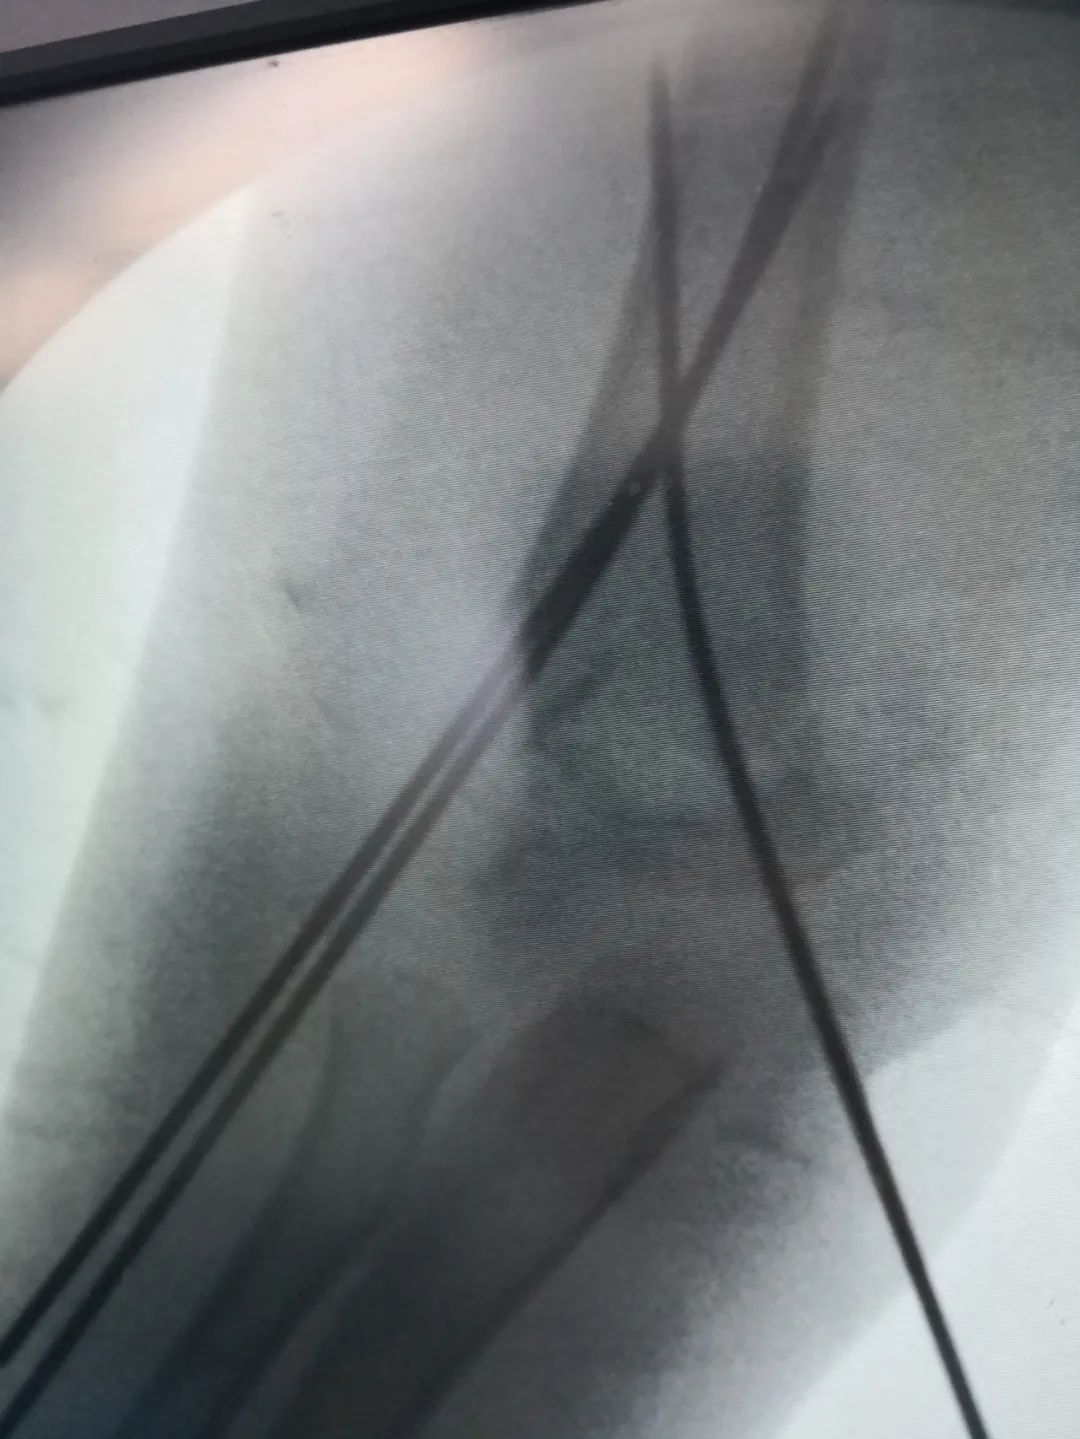

刘法银医生介绍称,经检查,童童诊断为右侧肱骨髁上骨折,软组织挫伤重,伴桡神经损伤,给予‘桡神经探查术+切开复位内固定术’。

“对于另外2例骨折患儿,因未造成神经损伤,给予C臂透视下手法复位闭合穿针内固定手术,不用切口,创伤小,恢复快,术后四周门诊拔出钢钉,免除二次手术取内固定。”刘医生说道。